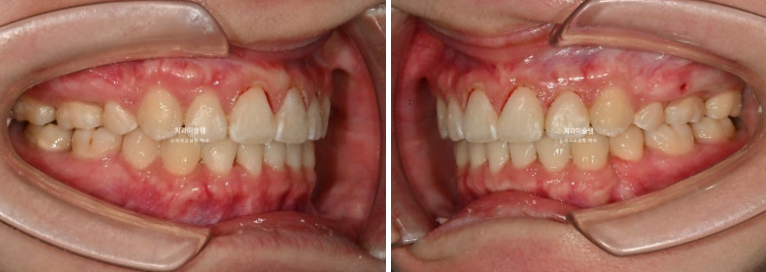

중심선은 잘 맞고 과개교합도 해소가 되었습니다.

어금니 교합은 물샐틈 없는 1급 교합관계 입니다.

23.08~25.11

옥니였던 위 앞니 각도가 개선이 되면서 미소가 한층 밝아졌습니다.

입은 계획대로 과하지 않게 적당히 들어갔습니다.